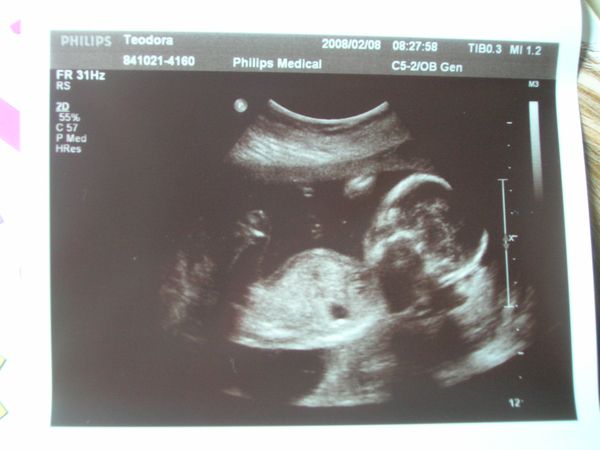

Én tegnap voltam 18 hetes genetikain ahol megerősítést kaptunk, hogy Dávidka Dávidka marad most már nincs mese

BPD:43mm THQ:39 mm ezeket mérték, az AFP értéke meg 1,21